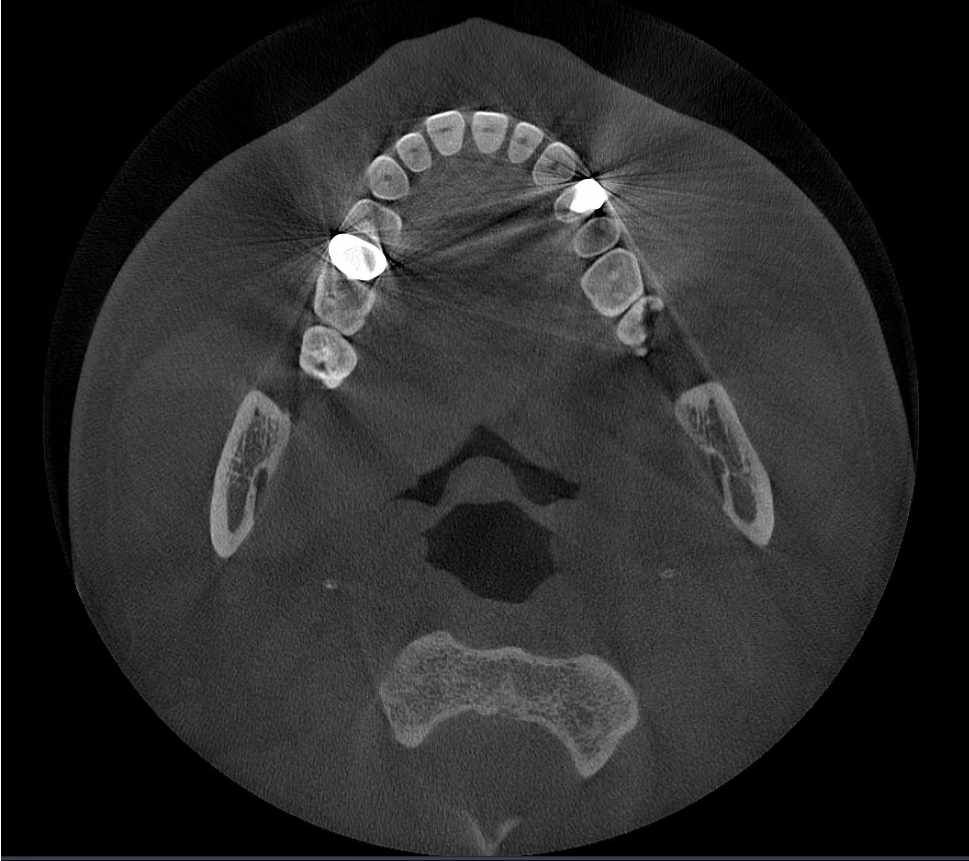

Các hiện vật kim loại được xóa bằng công nghệ AI và cấu trúc răng, mão kim loại và cấy ghép được phục hồi chính xác dựa trên các nguyên tắc toán học.

Không có MAR